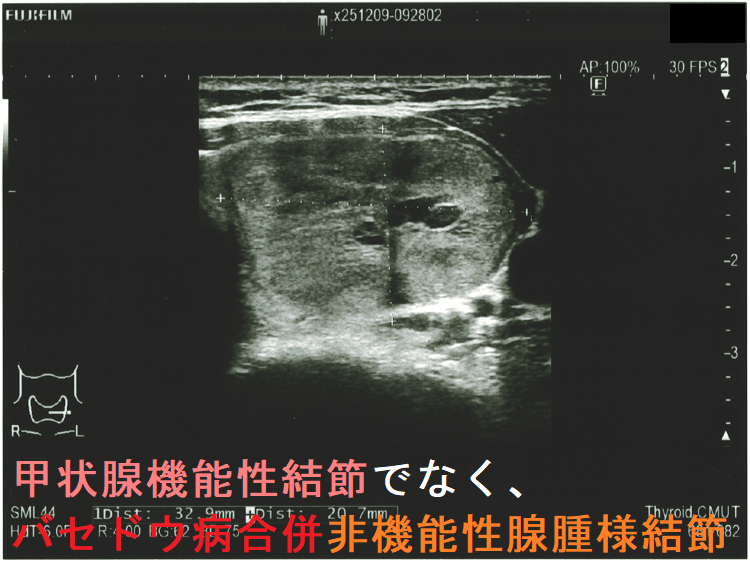

- 甲状腺機能性結節(機能性甲状腺腫)でなく、バセドウ病合併非機能性腺腫様結節だった

超音波(エコー)検査

機能性結節の74.1% は結節内および周辺の血流が豊富ですが、25.9%は周辺の血流のみが豊富です[Radiol Med. 1998 Mar;95(3):193-8.]。